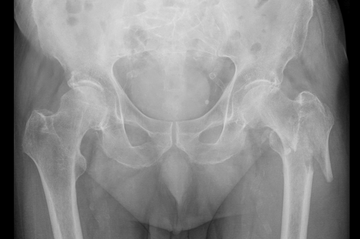

Hüftgelenksnahe Oberschenkelbrüche bezeichnen die knöchernen Verletzungen des Hüftkopfes, des Schenkelhalses oder des Rollhügelmassivs (Trochanter major und minor). In der Regel ist ein Sturz auf das Hüftgelenk oder ein direktes Anpralltrauma dafür verantwortlich. Diese Frakturen sind typische Frakturen des höheren Lebensalters.

Die Patienten werden fast ausnahmslos über die Rettungsstelle in unsere Klinik eingewiesen. Klassische Symptome sind die Gehunfähigkeit, starke Schmerzen und ein nach außen verdrehtes Bein. Lokale Blutergüsse sind häufig vorhanden.

Modernste radiologische Diagnostik steht uns zur Klassifizierung der Fraktur und der sich daraus ergebenden Therapie zur Verfügung.